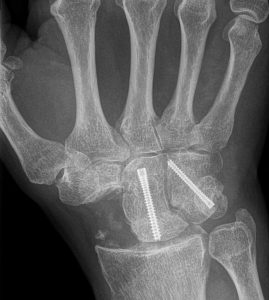

- Beeldvorming: met een röntgenfoto van de pols kan polsartrose bevestigd worden. Op de foto ziet men een versmalling van de gewrichtsruimte, botvergroeiingen (osteofyten) en soms standsafwijkingen van de polsbeentjes. In sommige gevallen wordt een CT-scan of MRI gemaakt om details van het gewricht en eventuele botschade beter in kaart te brengen.